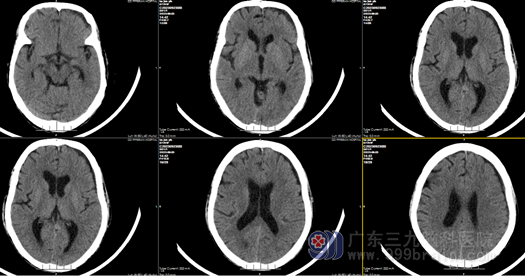

我院神经外十科欧阳辉教授接诊患者后,通过查体及详细询问其病史,结合患者颅脑CT 结果,诊断为“左侧额颞顶部慢性硬膜下血肿”,血肿如继续扩大,病情进展将有偏瘫可能,甚至会导改昏迷、脑疝。在患者入院后,欧阳辉教授带领团队进行了详细术前讨论与评估,最终确定了手术方案。向家属明确告知手术必要性和风险,获得充分理解并签字同意后,入院第2天外十科医生在全麻下行左侧慢性硬膜下血肿钻孔、冲洗,引流术”,手术顺利,患者手术后CT结果示:血肿已清除,柯奶奶术后很快神志清醒,言语对答切题,她未发生任何并发症和后遗症,手术3天后即可独立下床活动,伤口愈合良好,术后七天出院。回家后,奶奶又可以过上正常幸福的生活了。